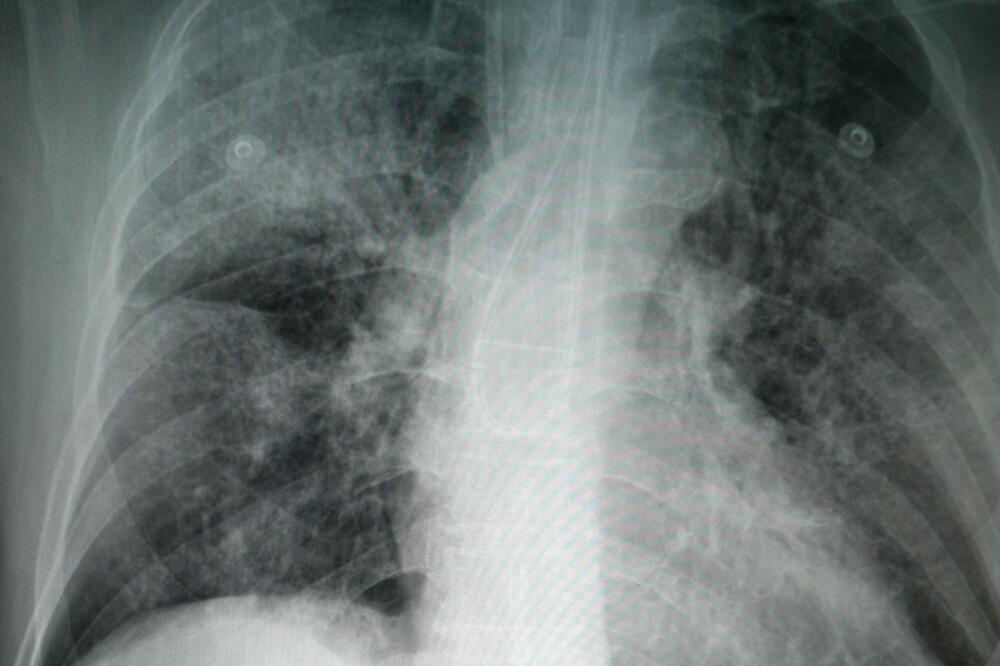

Krvni ugrušci mogu izazvati srčani udar, moždani udar, plućnu emboliju (PE), duboku vensku trombozu (DVT) i u najgorim slučajevima smrt.

DVT je krvni ugrušak koji se često formira u nozi, Dok je PE krvni ugrušak koji blokira krvni sud u plućima.

Oba stanja su ozbiljna i mogu dovesti do invaliditeta ili čak smrti.